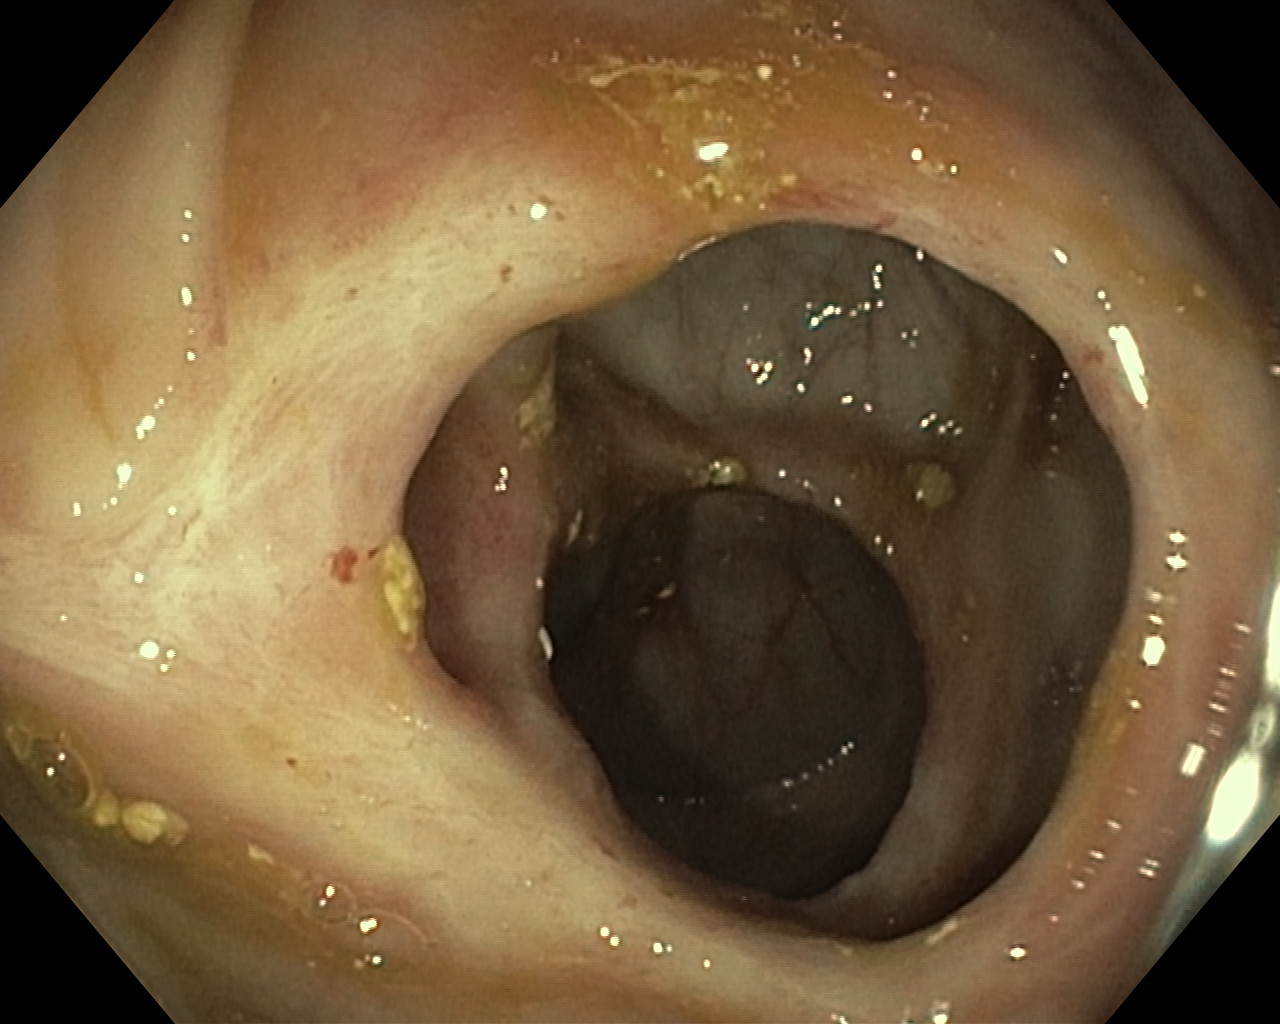

Obrazy endoskopowe

Choroba Leśniowskiego-Crohna